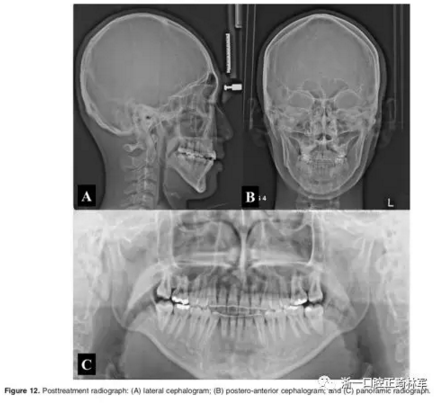

影像學:頭顱側位片示:矢狀向和垂直向骨骼發(fā)生變化(ANB角,3°;SN-MP,51°);上頜切牙略前傾(U1-SN,106°),與下頜切牙一致(IMPA,75°);病人的面部輪廓得以保持。全景片示:由于牙齒萌出,上前牙區(qū)垂直向牙槽骨水平增加;雖然前牙牙根較彎曲,但其平行度仍可,且無明顯的牙根吸收。CBCT示:前牙唇側骨質(zhì)連續(xù)性改善,牙根唇側支持組織變好,牙槽骨高度、厚度均有增加,但轉(zhuǎn)矩的改變一定程度上導致了局部應力的增大。